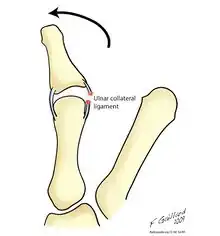

Gamekeeper's thumb and skier's thumb are two similar conditions, both of which involve insufficiency of the ulnar collateral ligament (UCL) of the thumb. The chief difference between these two conditions is that skier's thumb is generally considered to be an acute condition acquired after a fall or similar abduction injury to the metacarpophalangeal (MCP) joint of the thumb, whereas gamekeeper's thumb typically refers to a chronic condition which has developed as a result of repeated episodes of lower-grade hyperabduction over a period of time.[7] There are four types of Skier's thumb injury:[7]

In addition to skiing, this injury (resulting from forced abduction or hyperextension of the proximal phalanx of the thumb) is seen in a wide variety of other athletic endeavors. The most common mechanism of injury appears to be when a person extends the arm in an attempt to block a fall. The stress resulting from falling onto an abducted thumb produces a valgus force on the MCP joint of the thumb, resulting in a sprain or tear of the UCL.[8]

CS Campbell, an orthopedic surgeon, originally coined the term gamekeeper's thumb in 1955, after he observed this condition in a series of 24 Scottish gamekeepers.[10] The injury appeared to occur as a result of the particular manner in which they killed small animals such as rabbits; the animals were placed on the ground, and their necks were broken as the gamekeeper exerted downward pressure with the thumb and index finger. This maneuver would place a valgus force upon the abducted metacarpophalangeal (MCP) joint. Over time, this would lead to insufficiency of the ulnar collateral ligament (UCL) of the thumb.